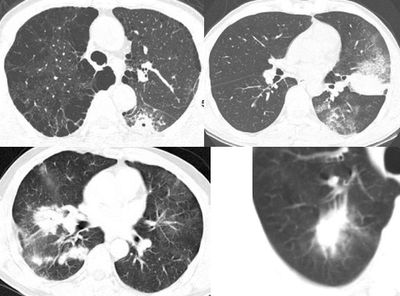

(1)发生部位:炎性假瘤可发生在两肺的任何部位,但多位于肺的表浅部位,邻近胸膜处或者靠近叶间裂。可以跨叶生长,原因可能是跨叶浸润的炎症使得假瘤跨叶融合的结果。

(2)假瘤形态:炎性假瘤的形态不一,可呈圆形.椭圆形或类圆形,也可呈驼峰状或不规则图形。

(3)假瘤大小:多数假瘤的直径在2-4cm,也可大于5cm,少数甚至大于10cm.

(4)假瘤密度:炎性假瘤一般为中等密度,密度均匀。而脓性炎症形成的假瘤则有时可见小空洞。空洞可以单发也可多发。少数瘤体切开时可见脓性物。

(5)假瘤边缘:

①有假无假性包膜者边缘清楚。有的由于肿块不规则可表现分叶状。

② 无假性包膜者,假瘤周围有纤维化和多种细胞成分侵润,表现为片状、边缘模糊的团块状影。或有轻度的渗出性病变,边缘模糊,以组织细胞围增生型多见。有的假瘤周围还可以出现类似周围型肺癌的放射冠状表现。

(6)邻近改变:位于肺周边部的假瘤,其邻近胸膜可见局限性粘连增厚。位于近肺门区的假瘤,偶可阻塞支气管,形成肺叶不张而将假瘤包裹,甚似中央性肺癌,但不出现肺门或纵膈淋巴结肿大。

3. 3. 5 分叶和毛刺 肺炎性假瘤的分叶多为浅小分叶,多数病变显示轮廓光滑锐利,靠近胸膜侧常伴有粗长毛刺与胸膜相连,局部胸膜可有不同程度的肥厚粘连,或由于假瘤周围多

次炎症而致边缘毛糙。

3. 3. 6 充气支气管征 在肺的炎性假瘤内可见充气支气管征[ 1 ] ,多为肺部炎性病变的一个重要特征,ct 扫描病变较易显示,必要时薄层扫描。